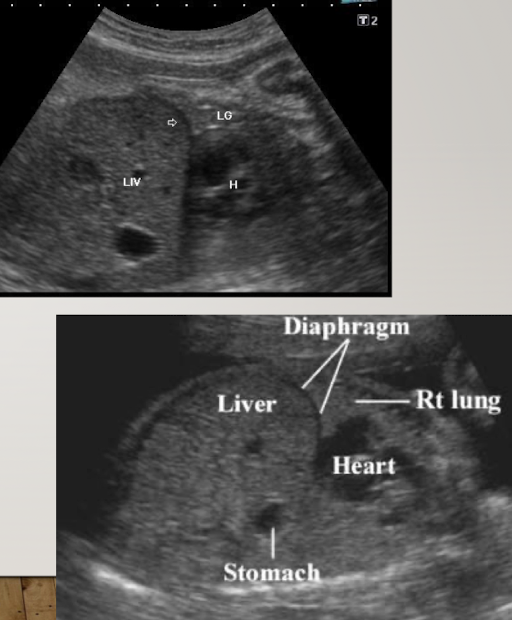

liver

large compared to other abdominal organs

occupies upper right abdomen

left lobe is larger in utero

SONO:

homogeneous, moderate echogenicity

helpful for determining situs and obtaining AC measurement

spleen

in LUQ

increases in size during gestation (biggest in 3rd trimester)

best images in TRV plane; to left of stomach

homogeneous

similar echogenicity to kidney

less echogenic than liver